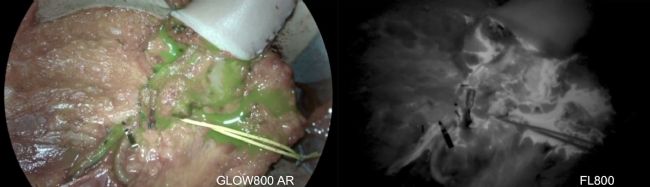

徠卡手術(shù)顯微鏡配置了ICG熒光攝像頭(FL800和GLOW800 AR熒光),強(qiáng)化了血液流動(dòng)檢查功能:

圖1:使用ICG熒光攝像頭GLOW 800(左側(cè))和熒光輔助血管造影術(shù)FL800(右側(cè))檢查血液流動(dòng)。